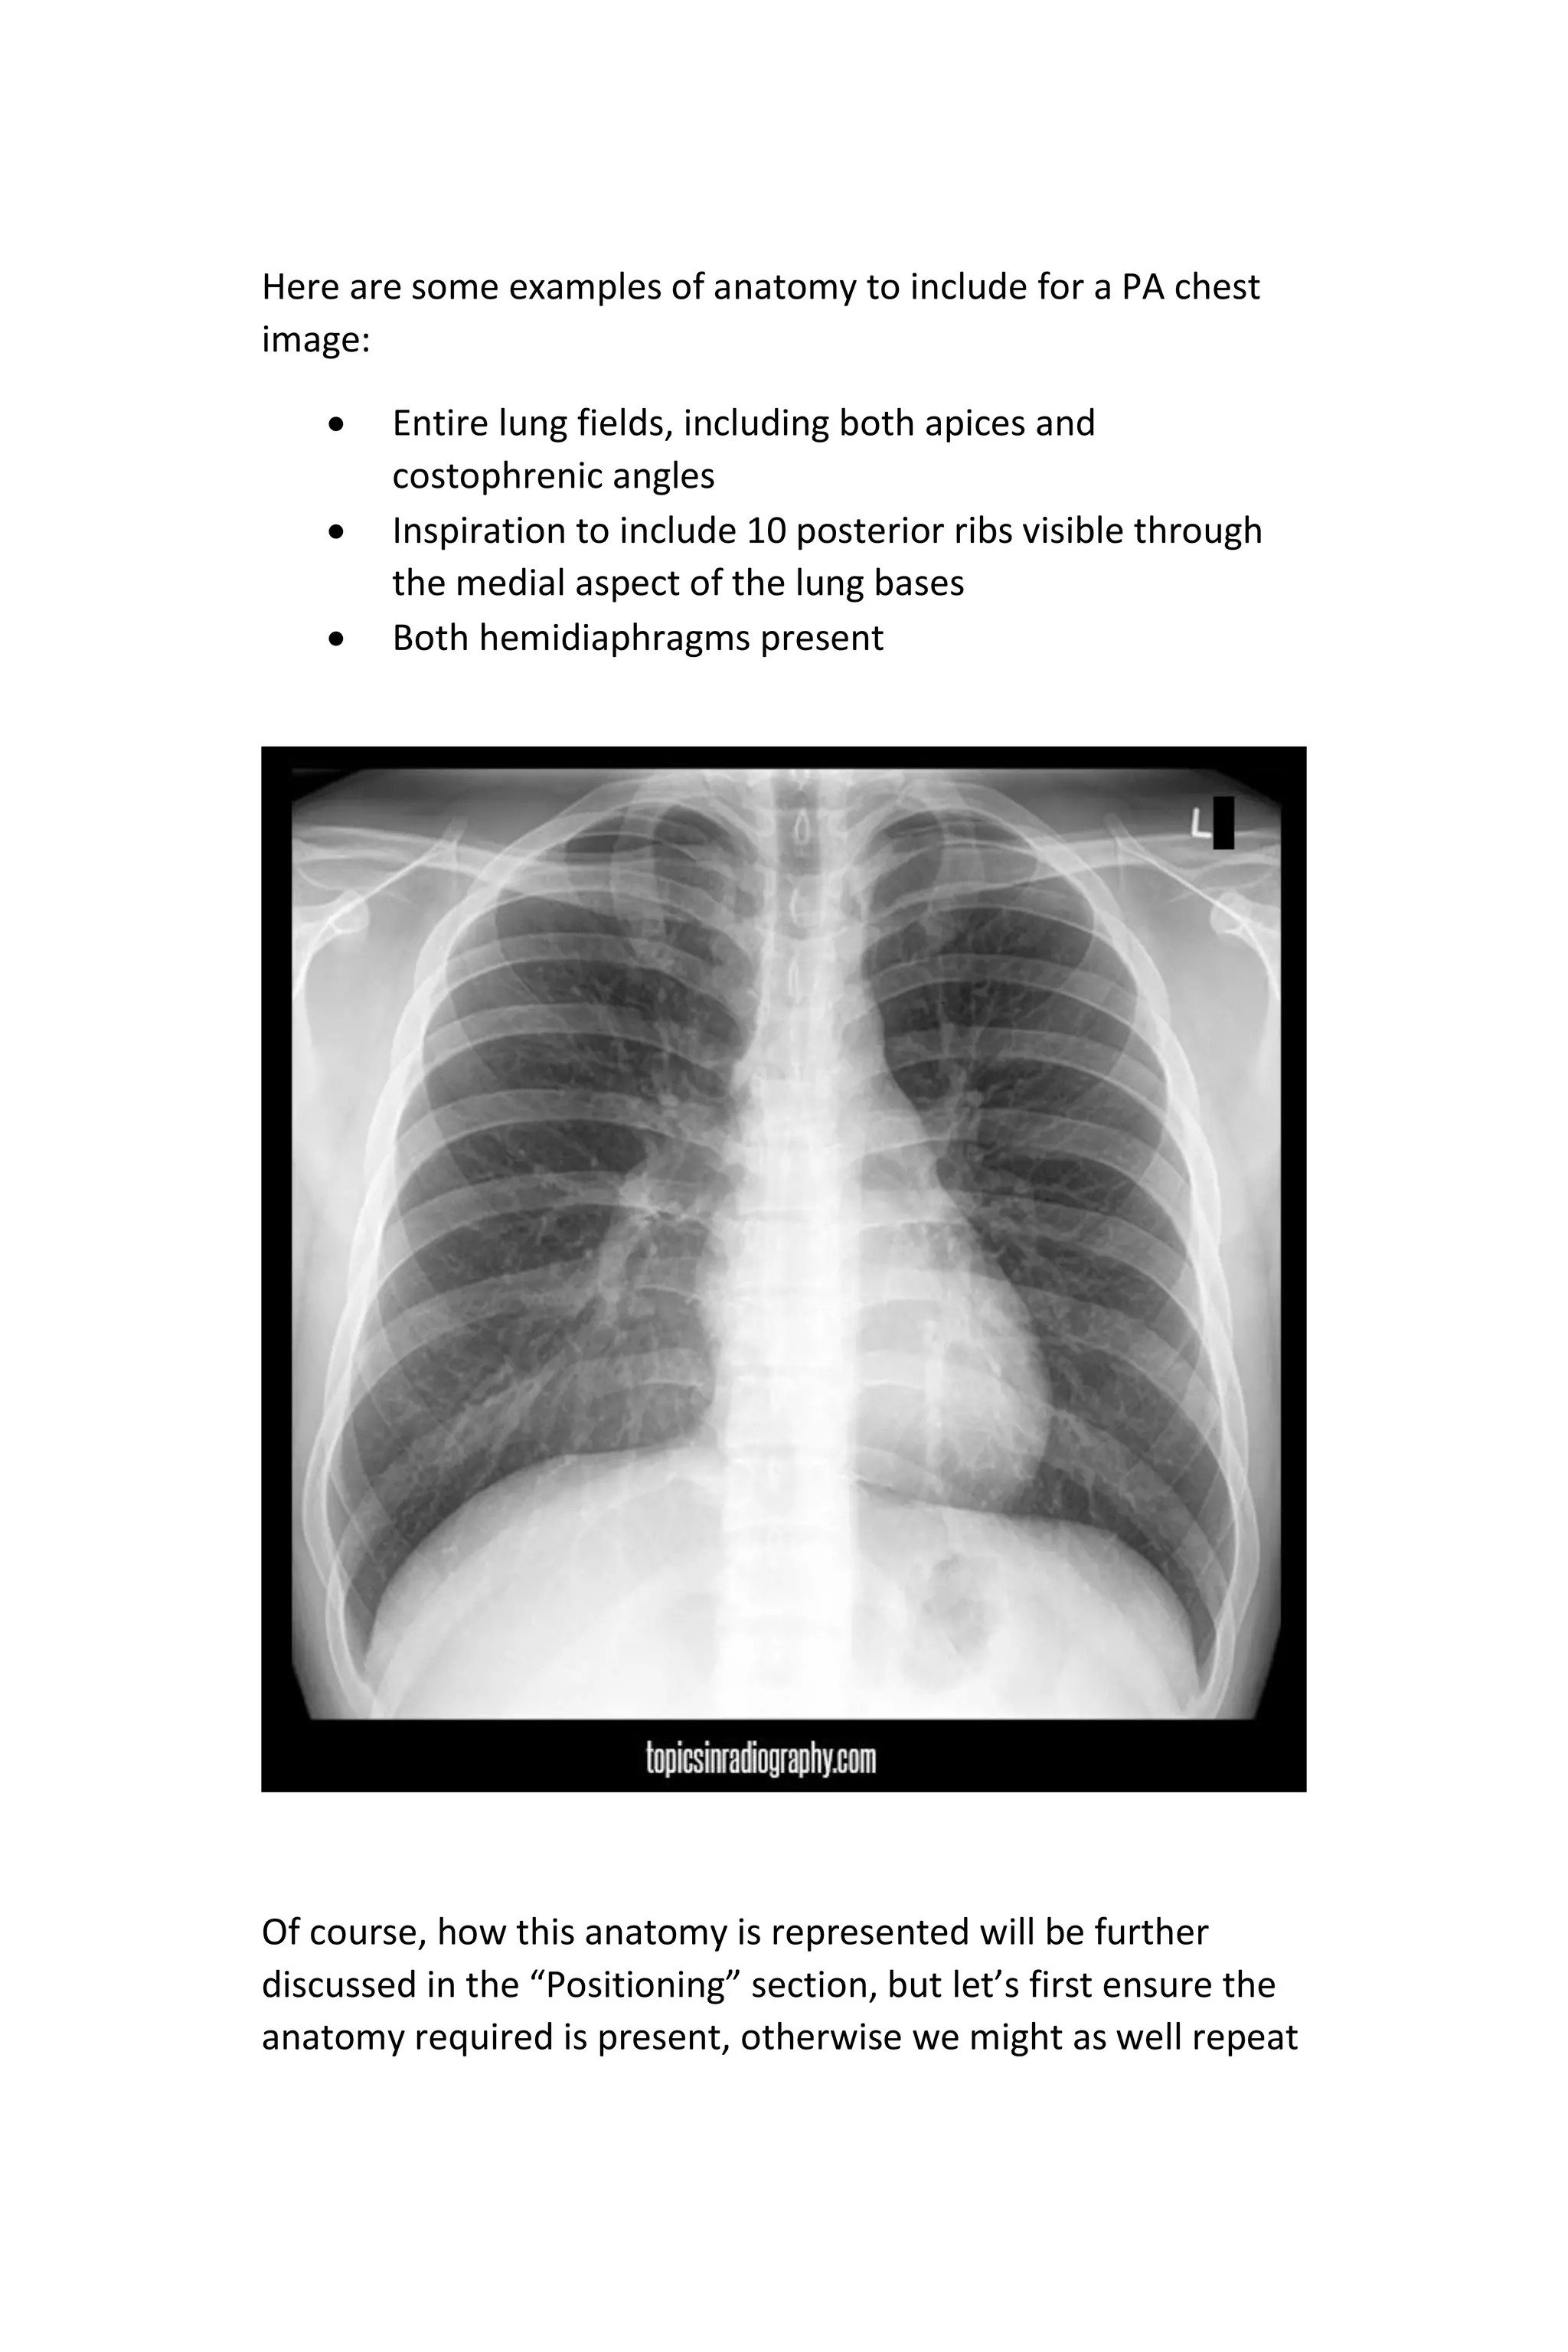

Since we typically perform more chest x-rays than any other

exam and it is usually the very first part taught in a radiography

positioning course, I will make an example of the PA or AP view

that any reader should be able to relate to.

Here are some examples of anatomy to include for a PA chest

image:

 Entire lung fields, including both apices and

costophrenic angles

 Inspiration to include 10 posterior ribs visible through

the medial aspect of the lung bases

 Both hemidiaphragms present

Of course, how this anatomy is represented will be further

discussed in the “Positioning” section, but let’s first ensure the

anatomy required is present, otherwise we might as well repeat

the exposure now. Failure to include all of the anatomy makes

up a large portion of most repeat rates today. There is no

software compensation for this, and 100% of the outcome is

within the radiographer’s control.